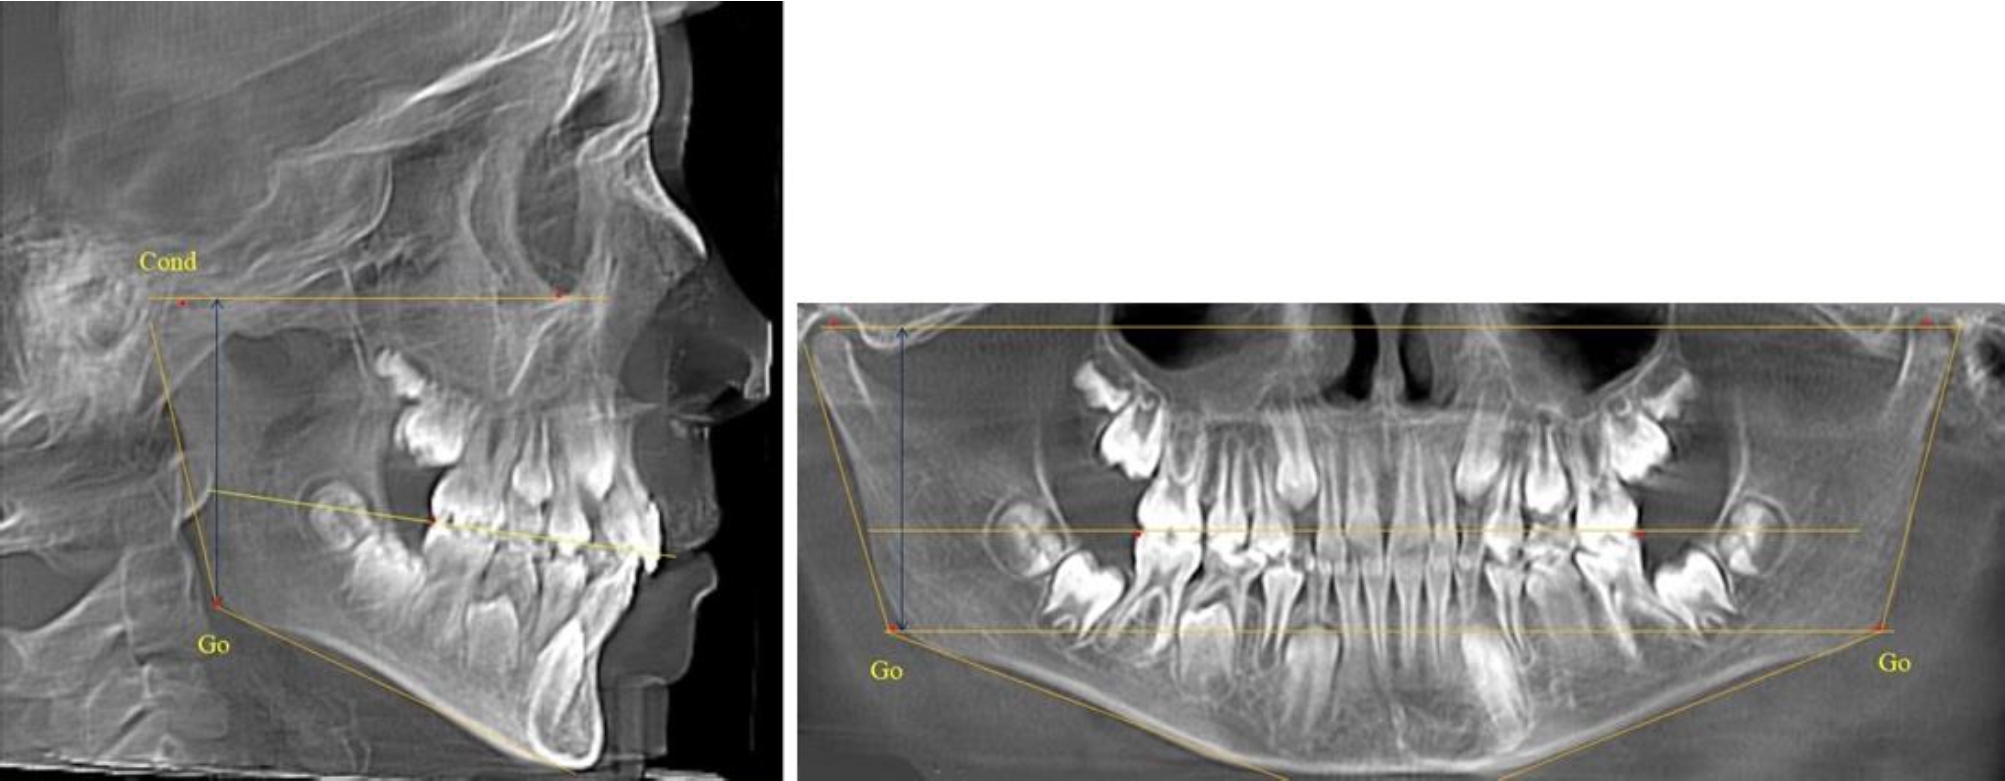

На всех парах рентгенограмм угол нижней челюсти, измеренный на телерентгенограмме, так же, как и в 1-й группе, соответствовал углу, полученному при построении угла на ортопантомограмме. Окклюзионная линия делила ветвь на два отдела (рис. 2).

Рис. 2. ТРГ и ОПТГ пациента после прорезывания первых постоянных моляров

Как на ортопантомограмме, так и на телерентгенограмме высота ветви у детей 2-й группы составляла (46,54 ± 2,87) мм, что было несколько больше, чем у детей 1-й группы (р ˂ 0,05). При этом высота верхней окклюзионно-суставной части была (25,42 ± 1,59) мм, а нижней – (21,12 ± 1,77) мм.

Таким образом, верхняя часть была несколько больше нижней, что и определяло рост обеих частей ветви.

Относительные показатели соразмерности частей ветви нижней челюсти показали, что отношение высоты верхней части ветви к нижней в среднем составляло 1,21 ± 0,12. Отношение общей высоты ветви к верхней ее части составляло 1,83 ± 0,13, а отношение общей высоты ветви к нижней ее части было 2,20 ± 0,16, и достоверных различий по относительному показателю отношения всей высоты к верхней и нижней челюсти нами не отмечено (р ˃ 0,05).